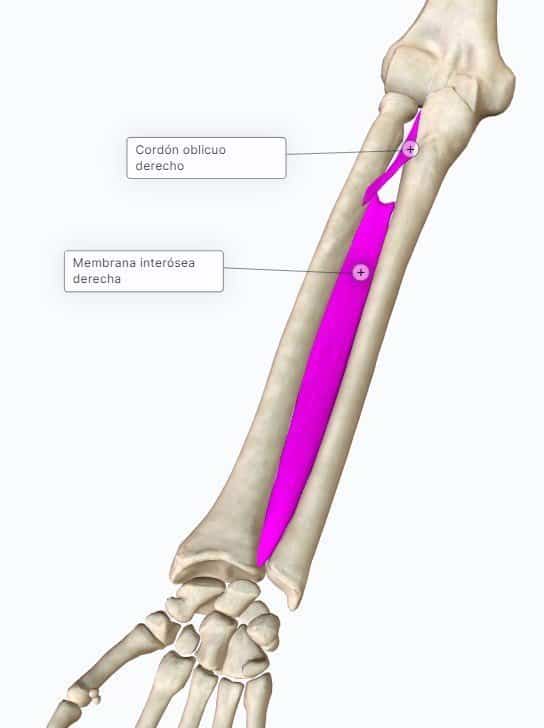

Membrana interósea: estructura y función

¿Qué es la membrana interósea del antebrazo y por qué es importante?

Sindesmosis que une radio y ulna

Fibras oblicuas dirigidas de radio a ulna, de proximal a distal

Funciones:

Transmite fuerzas del radio a la ulna (la mano empuja → radio recibe → fibras transmiten a ulna → distribuyen carga)

Aumenta superficie de origen muscular

Separa compartimento anterior del posterior

Cuerda oblicua (de Weitbrecht): fibras invertidas, proximal, refuerzo menor

Orificios: paso de arteria interósea anterior y posterior